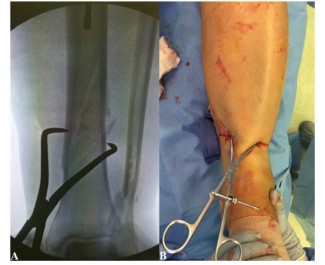

Однако устройство может оказывать значительную нагрузку на мягкие ткани, поэтому следует избегать длительного использования этого устройства для перенастройки. Редукционные щипцы также можно накладывать чрескожно, как при спиральных и косых переломах. Эти инструменты можно применять безвредно для мягких тканей через небольшие разрезы (рис. 7).

Рисунок 7. Чрескожный зажим для вправления перелома большеберцовой кости.